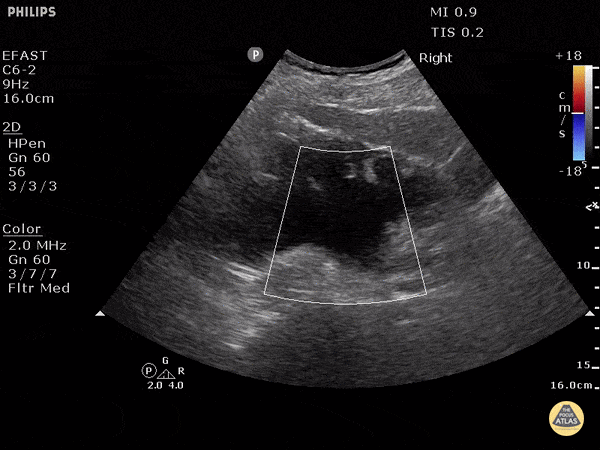

In this patient with severe hydronephrosis, there is gross dilation of both the renal pelvis and calyces, which are ballooned. The cortex of the kidney has atrophied and is very thin. This is severe, or grade 4. Dr. Justin Bowra et al. (Dr. Browne and Dr. Knights)